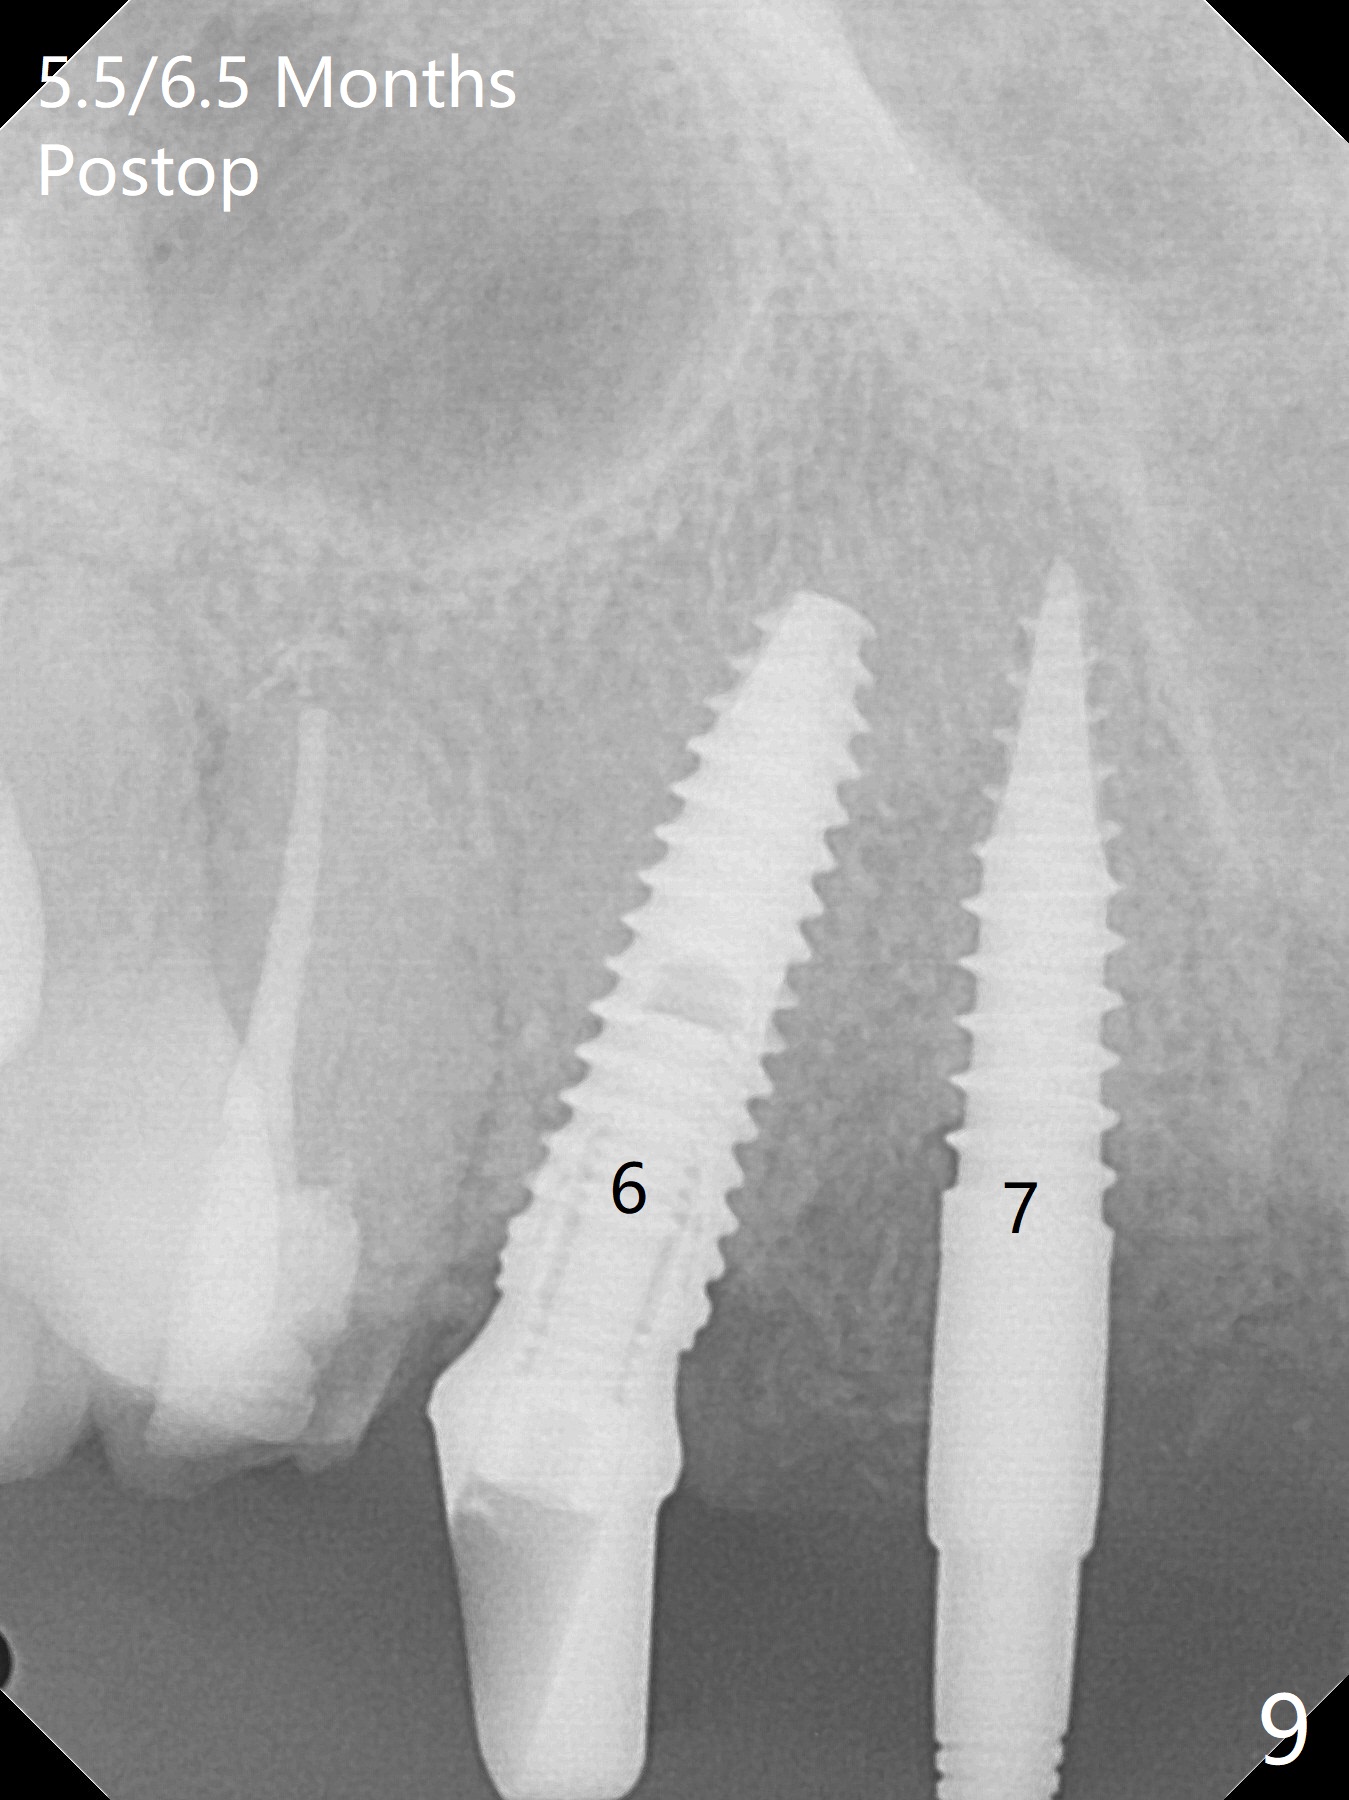

To have enough clearance for the splinted provisional at #6-12 (Fig.1 *), composite has been placed in the posterior teeth (bilateral, *, Fig.2). When the composite is removed, there is no clearance between the implants/abutments of #7 or 10 (Fig.3). Incision is made with removal of the 1-piece implant at #7; there is enough bone to move the osteotomy buccal (Fig.4 arrowhead). When the same implant is placed buccal (Fig.5), there is sufficient clearance for restoration (Fig.6 *), while there is still enough buccal bone left (Fig.7). When the patient returns 5.5 (for #7 and 10)/6.5 (#6,11,12) months postop, his chief complaint is tenderness lingual to #11. In fact, the abutment screw is loose at #11, while the implant at #10 has mobility (Fig.8), which is related to loss of the posterior stops (*) due to wear. There is slight bone loss mesial to #10 implant 5.5 months postop (Fig.10, as compared Fig.9). CBCT taken 5.5/6.5 months postop shows no bone loss (Fig.11-15). The 3x14 mm 1-piece implant at #10 is mobile 9 months postop and is removed and replaced by a 3.5x13 mm 2-piece one with slightly buccal osteotomy (Fig.16). PAs are taken prior to impression (Fig.17,18). The abutment at #12 is loose (<). More composite needs to be added to the occlusal surface of the upper posterior teeth. Finally the patient agrees to have crowns for the upper posterior teeth.